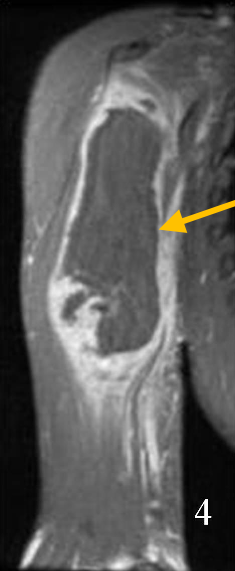

Liposarcoma is a malignant (cancerous) soft-tissue tumor that most commonly affects the extremities or the abdomen. They are the second most common soft-tissue sarcoma.